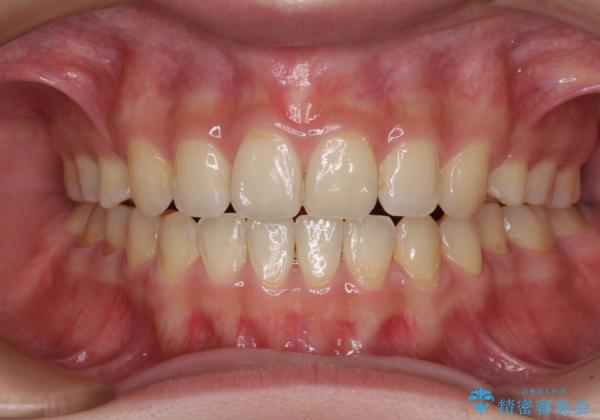

話しにくいオープンバイト ワイヤー装置による抜歯矯正治療

- 前歯のオープンバイトを気にして来院された患者様です。

上下前歯の前後位置が大きくずれていたため、上顎左右第一小臼歯2本を抜歯してワイヤー装置による矯正治療を行うこととしました。

オープンバイトの原因は舌の突出癖であり、癖が改善されないと治療経過に影響を及ぼすため、舌のトレーニングを指示しました。

なかなか癖が改善されず、トレーニングも断続的に行ったため、治療期間は長期化しました。